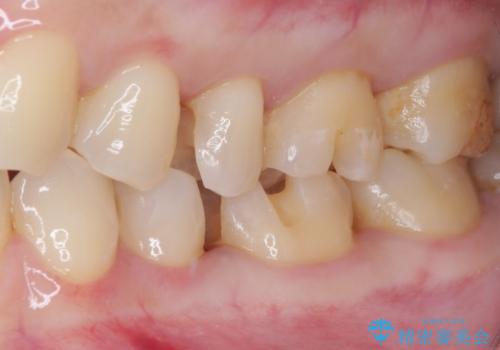

そして次の来院時、セラミックインレーを装着し、噛み合わせなどの調整を行います。

それを左右に分けて行いました。

インレーを装着するときは、唾液や血液による接着力の低下を避けるためにラバーダム防湿を行いました。

自然な色調で大変満足されました。